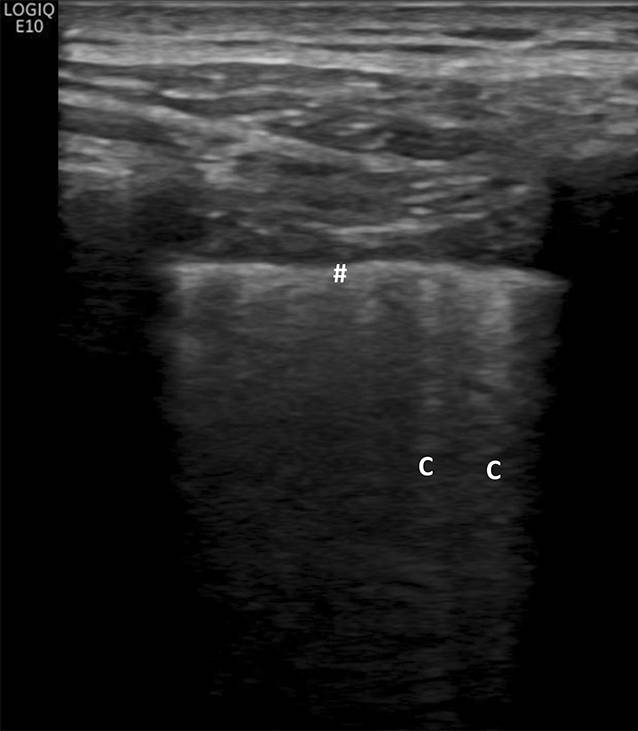

Diese Reverberationsartefakte werden sichtbar, wenn der Luftgehalt im Lungenparenchym teilweise reduziert ist bzw. das Volumen des interstitiellen Raums ausgeweitet ist, wie es im Rahmen des pulmonalen Ödems oder bei interstitiellen Lungenerkrankungen der Fall ist [3032]. Reverberationsartefakte werden in der Literatur als B‑Linien oder auch als Kometenschweifartefakte beschrieben und sind für sich genommen nicht spezifisch für bestimmte Erkrankungen (Abb. 3). Sie können aber im klinischen Kontext zur Frühdiagnose von Lungenveränderungen bei systemischer Sklerose und anderen interstitiellen Lungenerkrankungen herangezogen werden. In einer Konsensusarbeit der World Federation for Ultrasound in Medicine and Biology (WFUMB) wird empfohlen, Reverberationsartefakte, welche von einer glatten Pleura ausgehen (wie beim Lungenödem), als B‑Linien zu beschreiben, und Reverberationsartefakte, welche von einer verdickten oder unregelmäßigen Pleura ausgehen (wie bei interstitiellen Lungenerkrankungen), als Kometenschweifartefakte („comet tail artefacts“) zu beschreiben [21].

Abb. 3

Kometenschweifartefakte bei systemischer Sklerose. Raute Verdickte, irreguläre Pleuralinie, C Kometenschweifartefakte

Wesentliche Ultraschallmerkmale einer Lungenbeteiligung im Rahmen einer systemischen Sklerose sind Reverberationsartefakte, die von einer unregelmäßigen/fragmentierten Pleuralinie ausgehen und somit die Kriterien von Kometenschweifartefakten erfüllen. Es hat sich gezeigt, dass das Vorhandensein von 10 pro Interkostalraum oder mehr Kometenschweifartefakten als Cut-off-Point mit dem höchsten positiven Vorhersagewert für eine signifikante SSc-ILD entsprechend einem Warrick-Score ≥ 7 angesehen werden kann; die Sensitivität und Spezifität betragen 96,3 % bzw. 92,3 % [36].

Neben den Kometenschweifartefakten wird auch eine Verbreiterung der Pleuralinie auf ≥ 3 mm in jeglicher Region als pathologisch gewertet [23]. Als Pleuralinie wird die Grenzzone zur belüfteten Lunge beschrieben, bei der es zu einer Totalreflexion der Ultraschallwellen kommt. Obwohl die Pleura selbst aufgrund ihrer geringen Breite nicht durch den Ultraschall dargestellt werden kann, wird die Pleuralinie von vielen Autoren etwas vereinfacht mit der Pleura gleichgesetzt (Abb. 4).